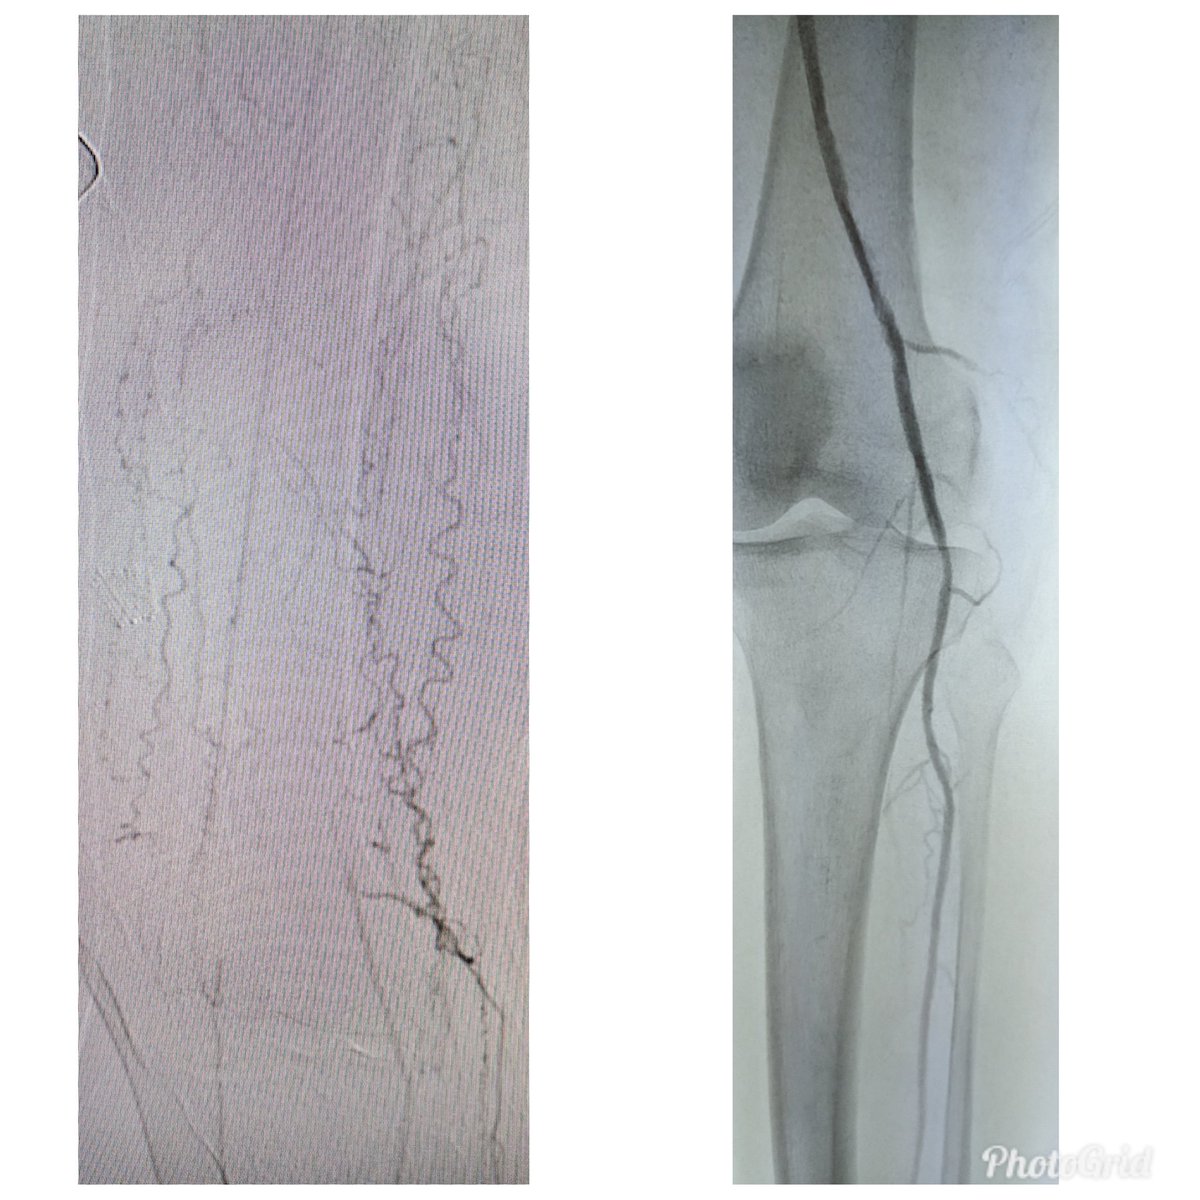

62 y/o F DM (HgA1c 14), plantar foot wound, OM of met head RC6 #CLI. #CSI @AbbottGlobal #commandwire #asahiregalia #POBA #Stopthechop #CLIfighters @Mustapja @FadiSaab17 @drsavealimb @SriniTummala @BOlivieriMD @DrBTKatzen @DrBobBeasley @keithppereira @kmadass @SDhandMD @JVIRmedia

Reconstruction of below knee occlusions are so satisfying. #pad @CLIFightersBot #stopthechop @AMPSymposium #commandWire